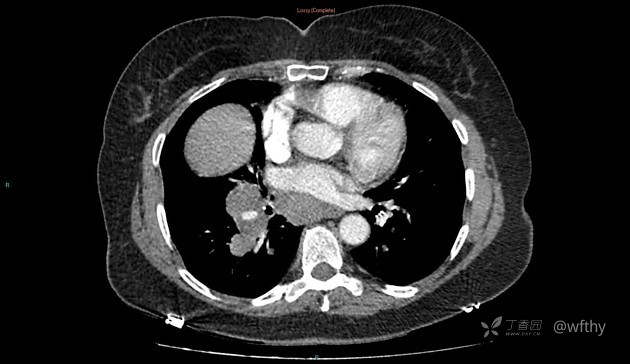

病例女65,头部肿块